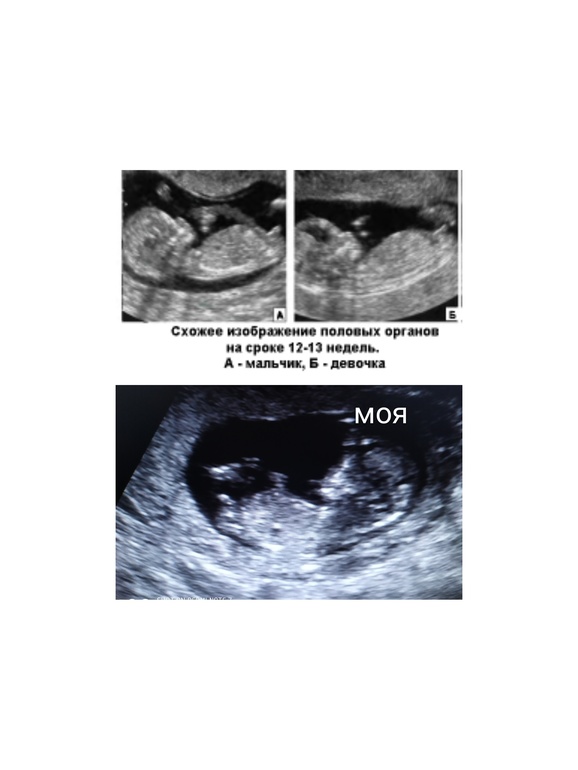

У нас вот такая же проблема...на двух УЗИ была, на первом девочку пообещали...а на втором в 13 недель врач сказал мальчик. А мне так доченьку хочется ( уже 2 сына) вот наше фото с первого скрининга

Не пойму))) а как по пузику и головке можно понять)) нужна проекция с низу попки

Говорят по изгибы хвостики, у мальчиков он сильнее вверх поднят